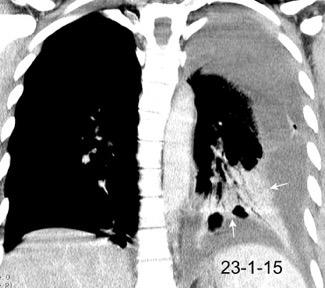

Marzo 2014: Perforación longitudinal distal secundaria a episodio de vómito (síndrome de Boerhaave). Derrame pleural izdo. que evoluciona a empiema.

Wang C-T et al. Tension hydropneumothorax in a Boerhaave syndrome patient: A case report . World J Emerg Med, 2021. Katabathina V et al. Nonvascular, nontraumatic mediastinal emergencies in adults:a comprehensive review of imaging findings. Radiographics. 2011.